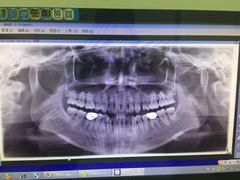

• 德伦口腔

• -德伦口腔